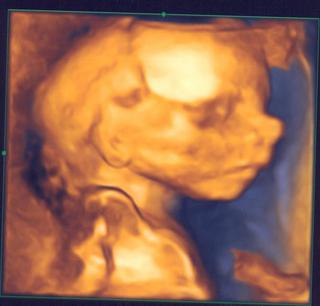

@katy2 kraaasny je a foto ti vyslo supeer 🙂 a ten nostek,ako ten nas taky horenos 😀 je rozkosny 😵

jéééj, holky, věříte mi, že jsem úplně mimo z toho druhýho miminka????? zase! každou chvilku chodím dostlova civět na fotky obou mých broučků -Štěpánka a překvapení 🙂.... furt je porovnávám!!! no řekněte samy! nejsou si podobní?? jen ta Štěpíkova fotka je trochu zřetelnější, ale obě jsou z morfa a jsou jen zrcadlově otočené 🙂... koťátka moje.. dnes jsme měli se Štěpou takovej extra mazlivej den! furt chodil pusinkovat a mazlit se 🙂.. to se pro ty děti obě asi už rozplynu!! 🙂

Jinak jsem tu viděla další fotky z 3D -jsou překrásný!!! 😀 .. jen si nepamatuju kdo je tu má 😅 ...

@bettyx aj mne sa zdá ze sa tvoji drobci podobajú 🙂

@katy2 gratulujem k chlapčekovi, vyzerá nádherne

@bettyx rozkosne,ja som to nase video tiez uz videla asi 20x 😵 moj muz ked zbadal na obrazovke nase male hned povedal,ze vyzera ako nas prvy risko....mne sa moc nezda,mne sa zda ze je cely tato 😀 uvidime ked sa narodi na koho sa podoba....